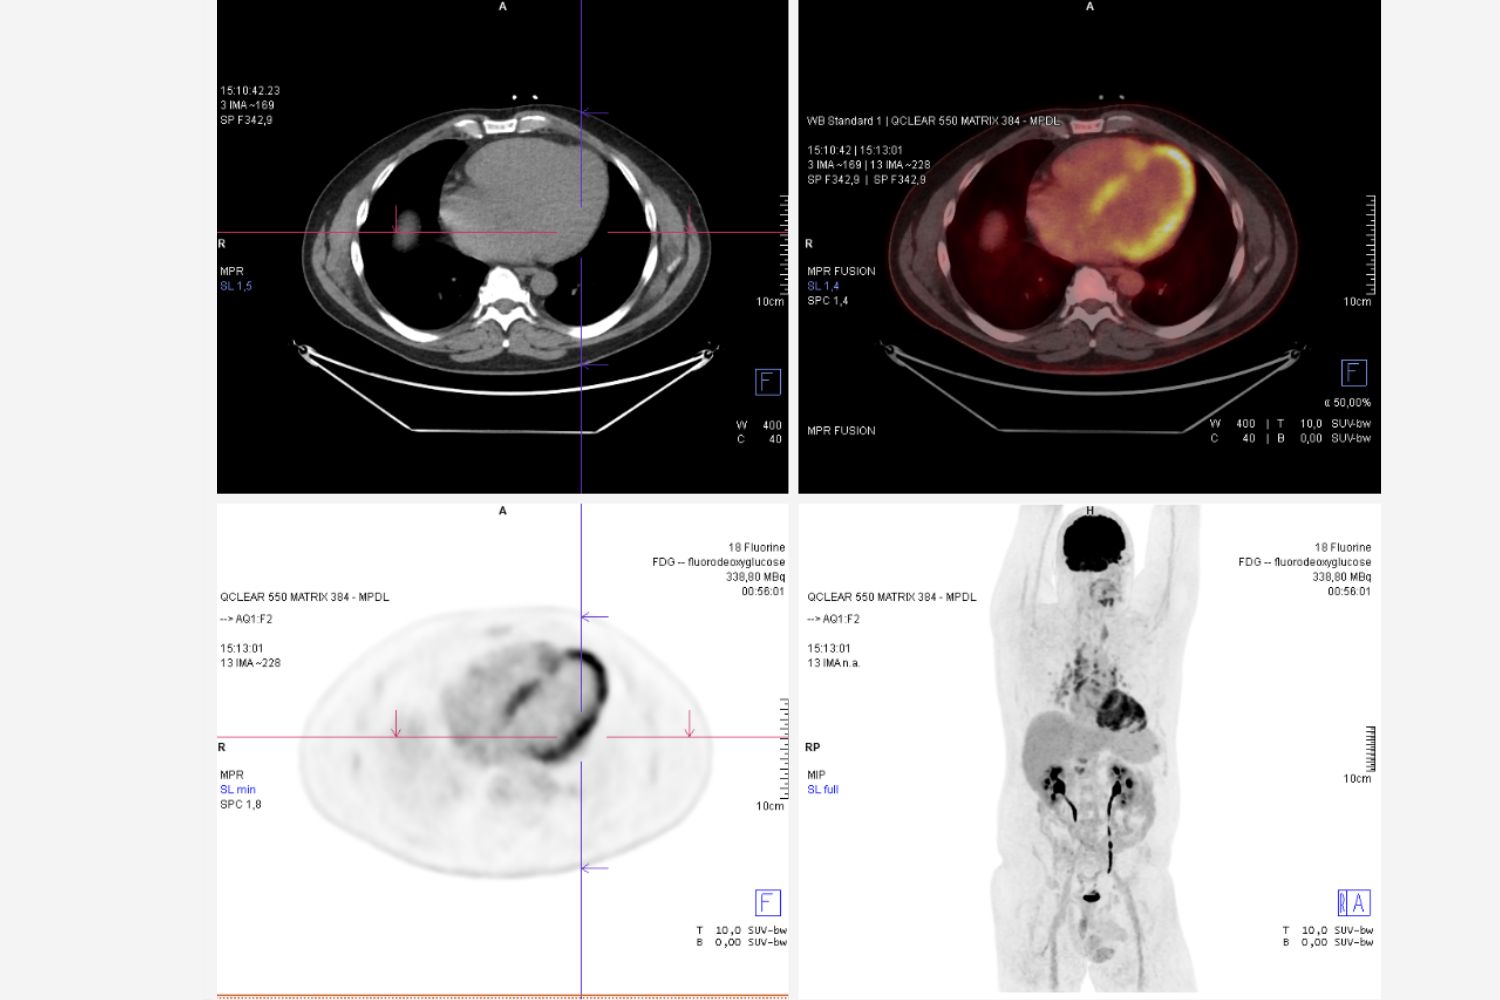

Image of the Week - 23 July 2025

Image of the week